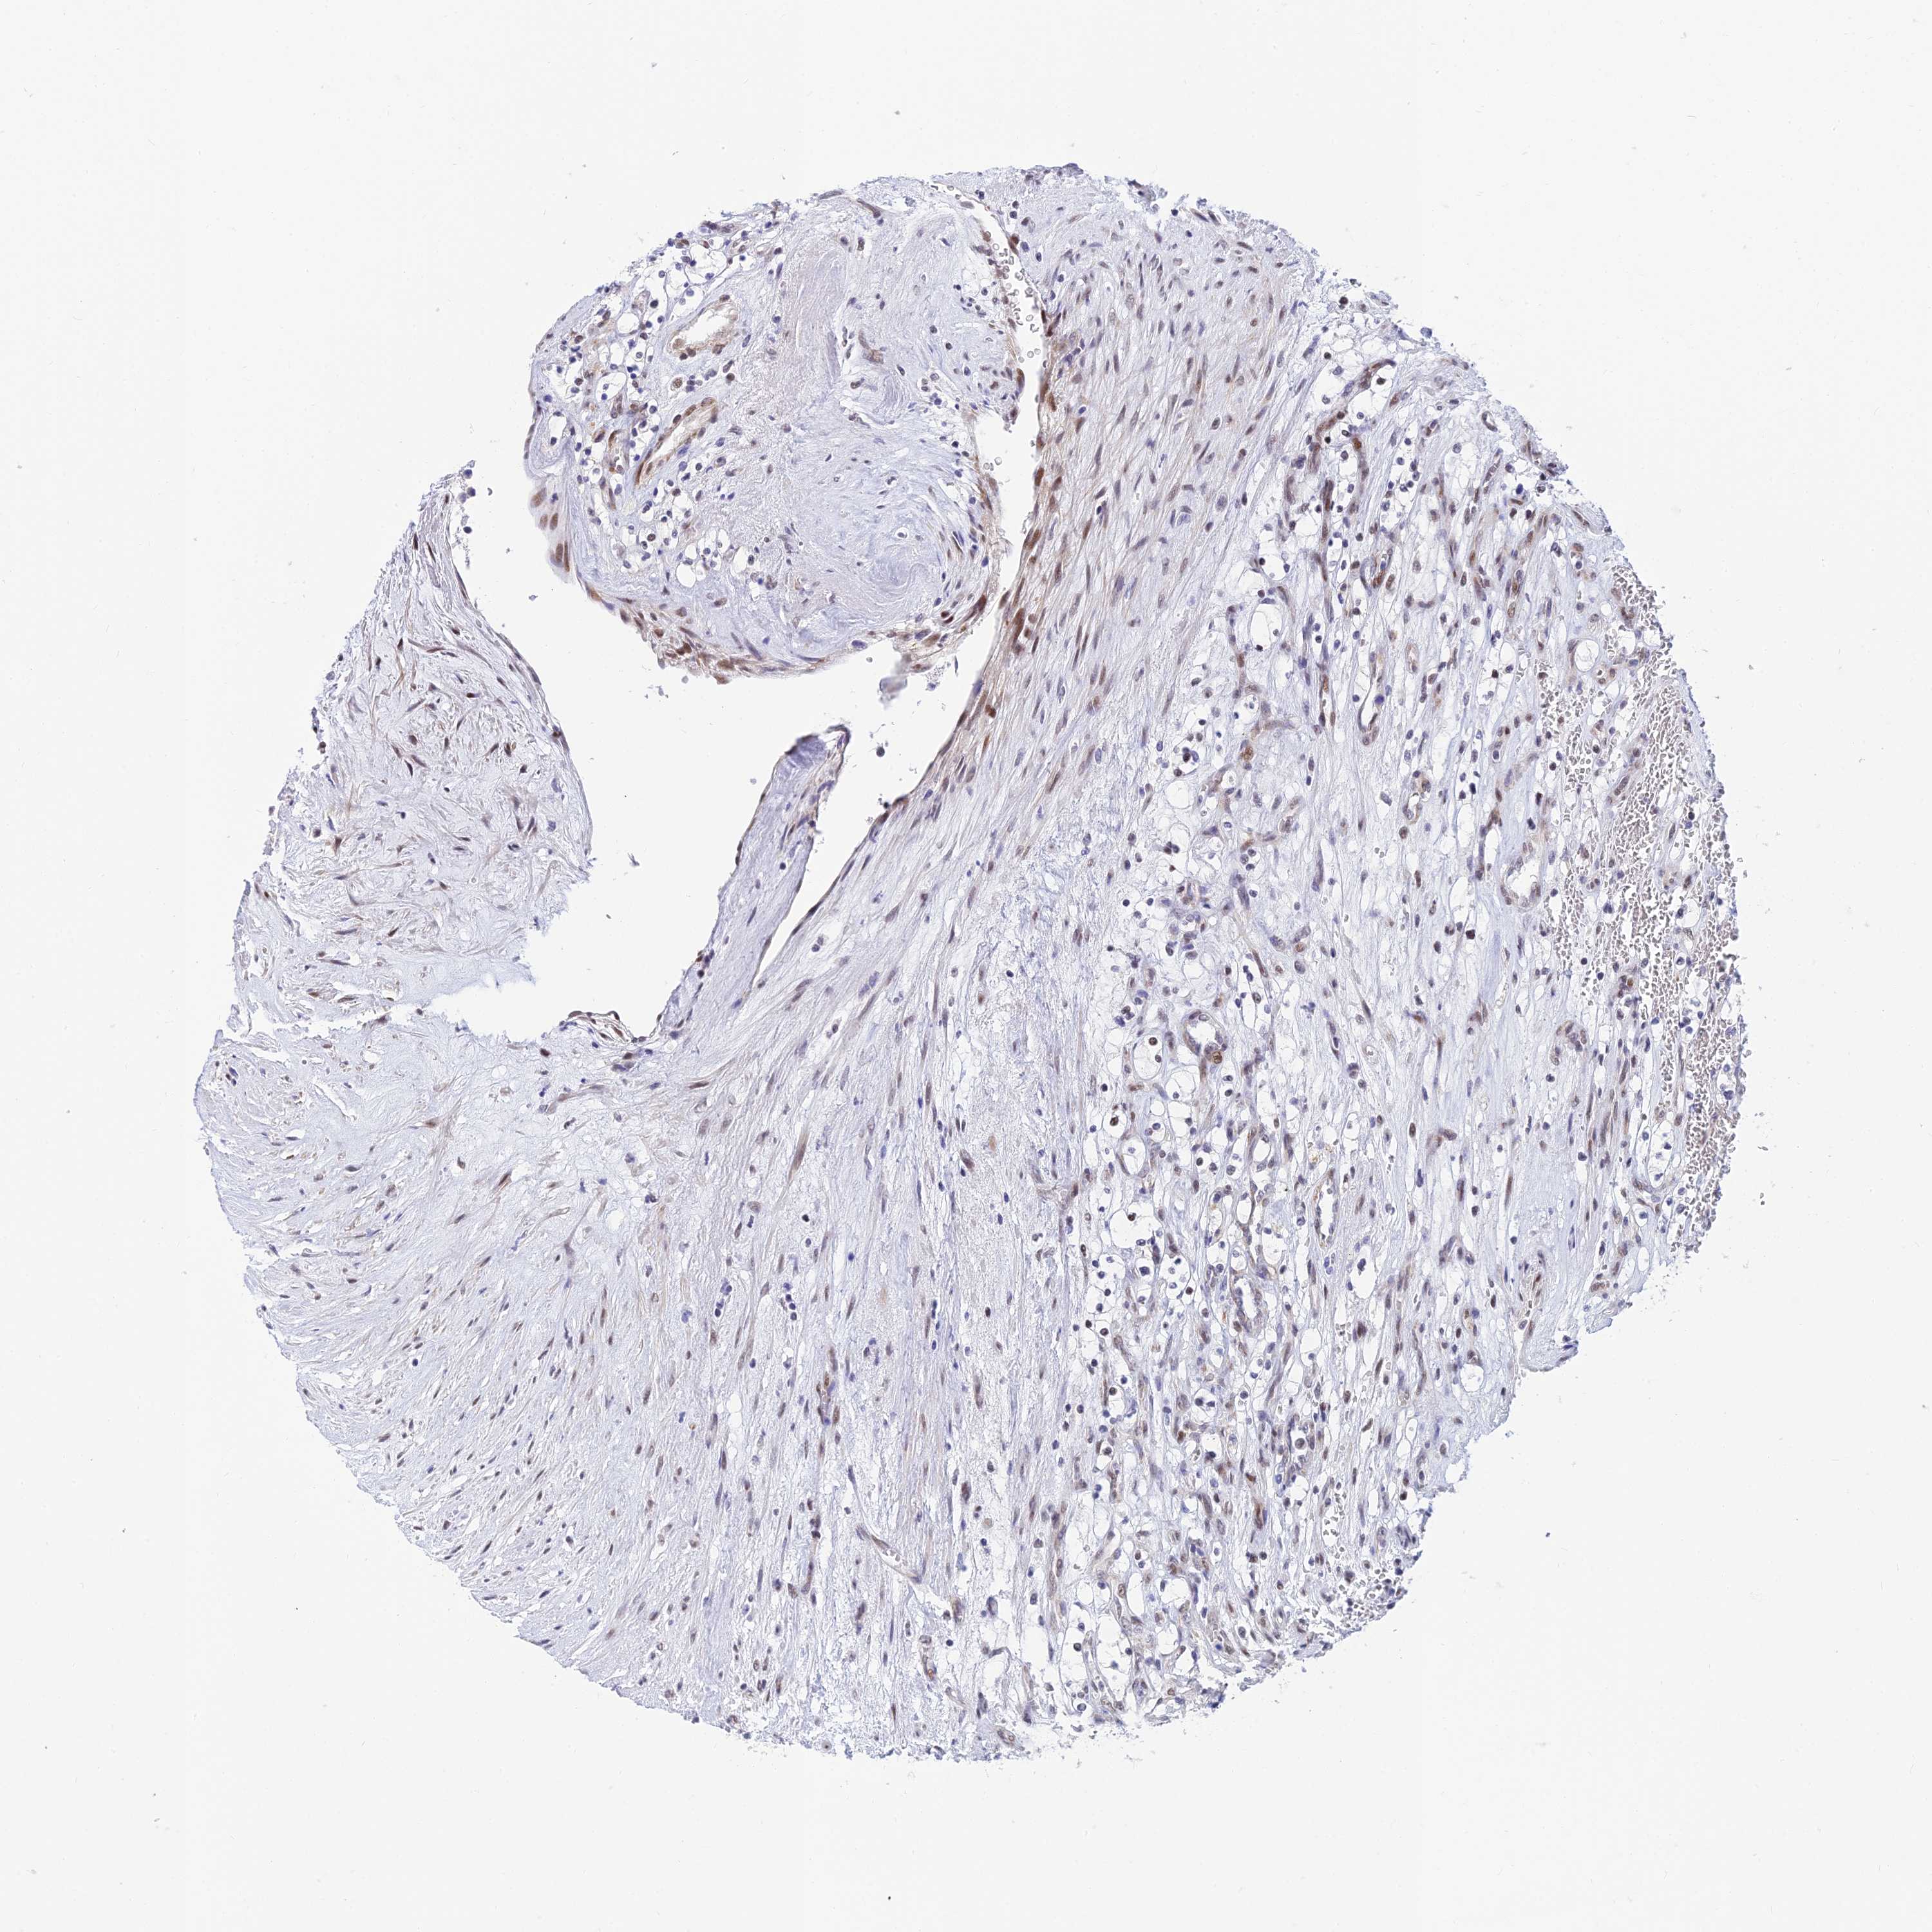

KIDNEY RENAL CLEAR CELL CARCINOMA (VALIDATION) - Interactive survival scatter ploti

The Survival Scatter plot shows the clinical status (i.e. dead or alive) for all individuals in the patient cohort, based on the same data that underlies the corresponding Kaplan-Meier plots. Patients that are alive at last time for follow-up are shown in blue and patients who have died during the study are shown in red.

The x-axis shows the expression levels (FPKM) of the investigated gene in the tumor tissue at the time of diagnosis. The y-axis shows the follow-up time after diagnosis (years). Both axes are complimented with kernel density curves demonstrating the data density over the axes. The top density plot shows the expression levels (FPKM) distribution among dead (red) and alive patients (blue). The right density plot shows the data density of the survived years of dead patients with high and low expression levels respectively, stratified using the cutoff indicated by the vertical dashed line through the Survival Scatter plot. This cutoff is automatically defined based on the FPKM cutoff that minimizes the p-score. The cutoff can be changed by dragging the vertical line or by entering a cutoff value in the square labeled "Current cut-off".

Under the Survival Scatter plot the p-score landscape (black curve; left axis) is shown together with dead median separation (red curve; right axis). Dead median separation is the difference in median mRNA expression between patients who have died with high and low expression, respectively. It is calculated as follows: median FPKM expression of dead patients with high expression - median FPKM expression of dead patients with low expression. This is intended to aid the user in visually exploring custom cutoffs and the associated p-scores and dead median separation.

Individual patient data is displayed and can be filtered by clicking on one or more of the category buttons on the top of the page. Categories describing expression level and patient information include: high, low, alive, dead, female, male and tumor stages. The scale of the x-axis can be toggled between linear and log-scale by clicking on the "x log" button. Mouse-over function shows TCGA ID, patient information and mRNA expression (FPKM) for each patient.

& Survival analysisi

Kaplan-Meier plots summarize results from analysis of correlation between mRNA expression level and patient survival. Patients were divided based on level of expression into one of the two groups "low" (under cut off) or "high" (over cut off). X-axis shows time for survival (years) and y-axis shows the probability of survival, where 1.0 corresponds to 100 percent.

CLK4 is potential prognostic, high expression is favorable in Kidney Renal Clear Cell Carcinoma (validation)

Best expression cut offi

Based on the FPKM value of each gene, patients were classified into two groups and association between prognosis (survival) and gene expression (FPKM) was examined. The best expression cut-off refers the FPKM value that yields maximal difference with regard to survival between the two groups at the lowest log-rank P-value. Best expression cut-off was selected based on survival analysis .

When clicking on this number, the vertical dashed line indicating cut-off, the interactive survival plot, and the Kaplan-Meier curve will be adjusted to show results based on the best expression cut-off.

: 14.62

TCGA RNA samplesi

RNA-seq data is reported as average FPKM (number Fragments Per Kilobase of exon per Million reads), generated by the The Cancer Genome Atlas (TCGA) .

Normal distribution across the dataset is visualized with box plots, shown as median and 25th and 75th percentiles. Points are displayed as outliers if they are above or below 1.5 times the interquartile range. FPKM values of the individual samples are presented next to the box plot.

Average pTPM 24.4

Number of samples 100